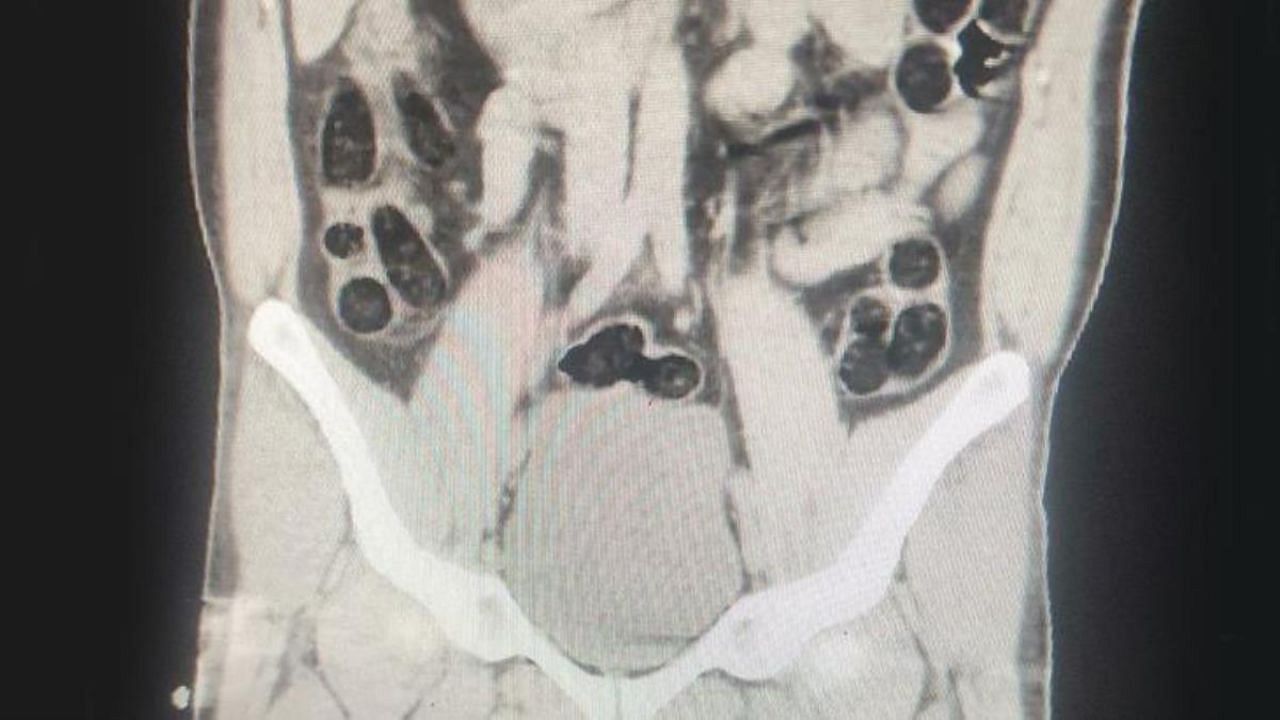

Operasyonda; otobüs ile seyahat eden 2 İran uyruklu şahsın yapılan kontrollerinde ve iç beden muayenesi sonucunda, şahıslardan birinin midesinde 76 paket halinde 714 gram uyuşturucu madde ele geçirildi.